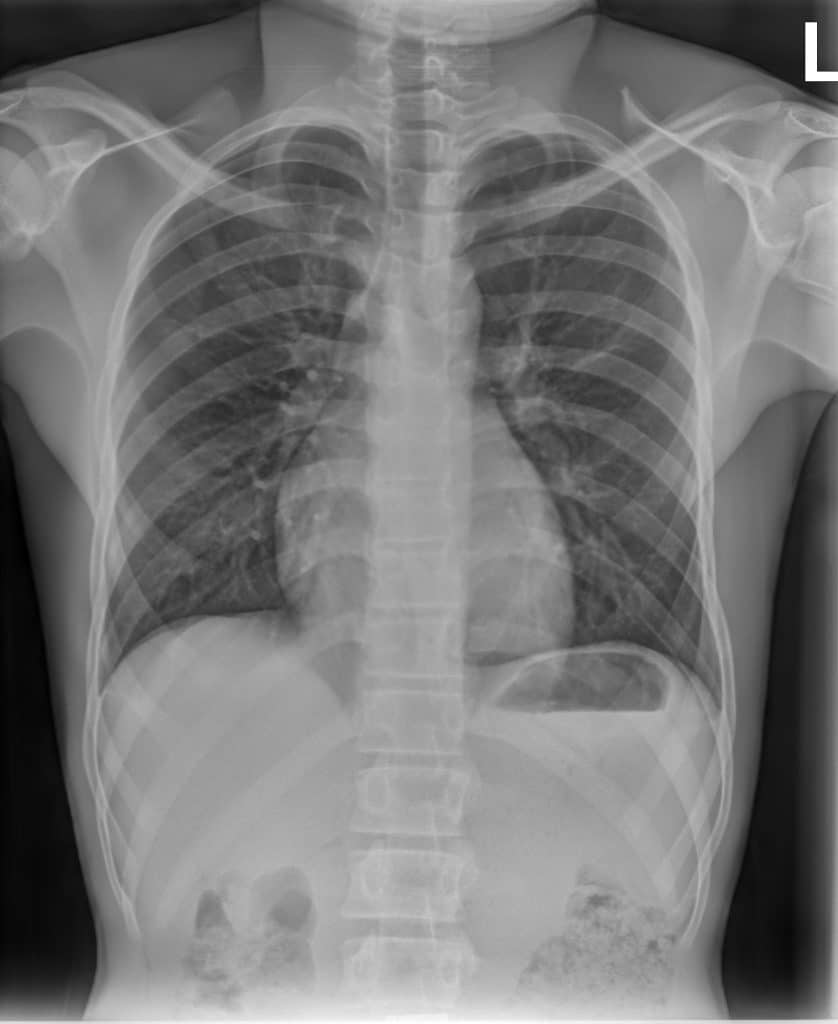

Reveal™ detectors generate three images from a single X-ray exposure:

- conventional radiograph

- bone image

- soft-tissue image

These images allow clinicians to examine anatomical structures from different perspectives and may provide additional insight when evaluating radiographs in environments where other imaging modalities are not available.